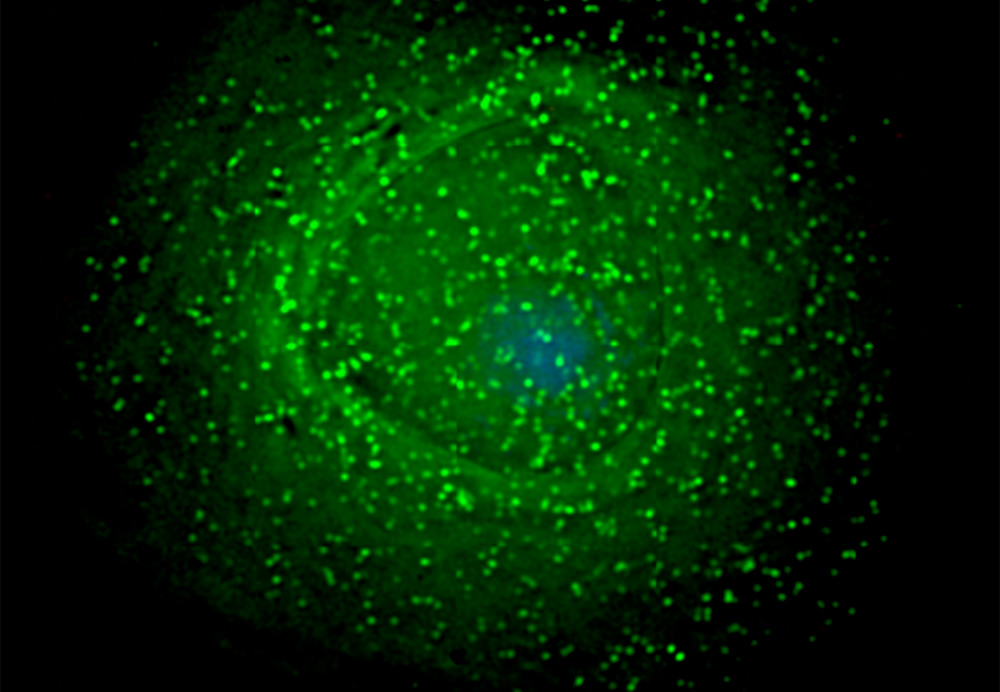

В ходе исследования учёным удалось обнаружить, что макрофаги защищают себя от ВИЧ, синтезируя специальный противовирусный белок SAMHD1. Некоторые вирусы могут его «выключать», но конкретно ВИЧ на это не способен. Тем не менее, существует механизм, благодаря которому вирус иммунодефицита проникает внутрь макрофагов.

Дело в том, что иногда этот белок «выключается» сам по себе. Учёные пока не могут точно сказать, почему это происходит.

Ведущий автор исследования Равиндра Гупта (Ravindra Gupta), профессор Отделения инфекций и иммунитета (Division of Infection and Immunity) Университетского колледжа Лондона поясняет: «Мы знали, что SAMHD1 «выключается» в процессе деления клеток. Но макрофаги не делятся, поэтому защитная работа белка в этих клетках, теоретически, не должна прерываться.

Однако нам удалось установить, что уязвимость, возникающая вследствие «выключения» SAMHD1 — это часть процесса нормальной жизнедеятельности макрофагов».

Хотя точная механика процесса пока неясна, исследователи предположили, что макрофаги сами «выключают» белок, когда им нужно провести процесс восстановления ДНК. Руководствуясь этой гипотезой, учёные обработали клетки ингибиторами гистондеацетилазы, веществами, непосредственно влияющими на укладку ДНК через взаимодействие с белками-гистонами.